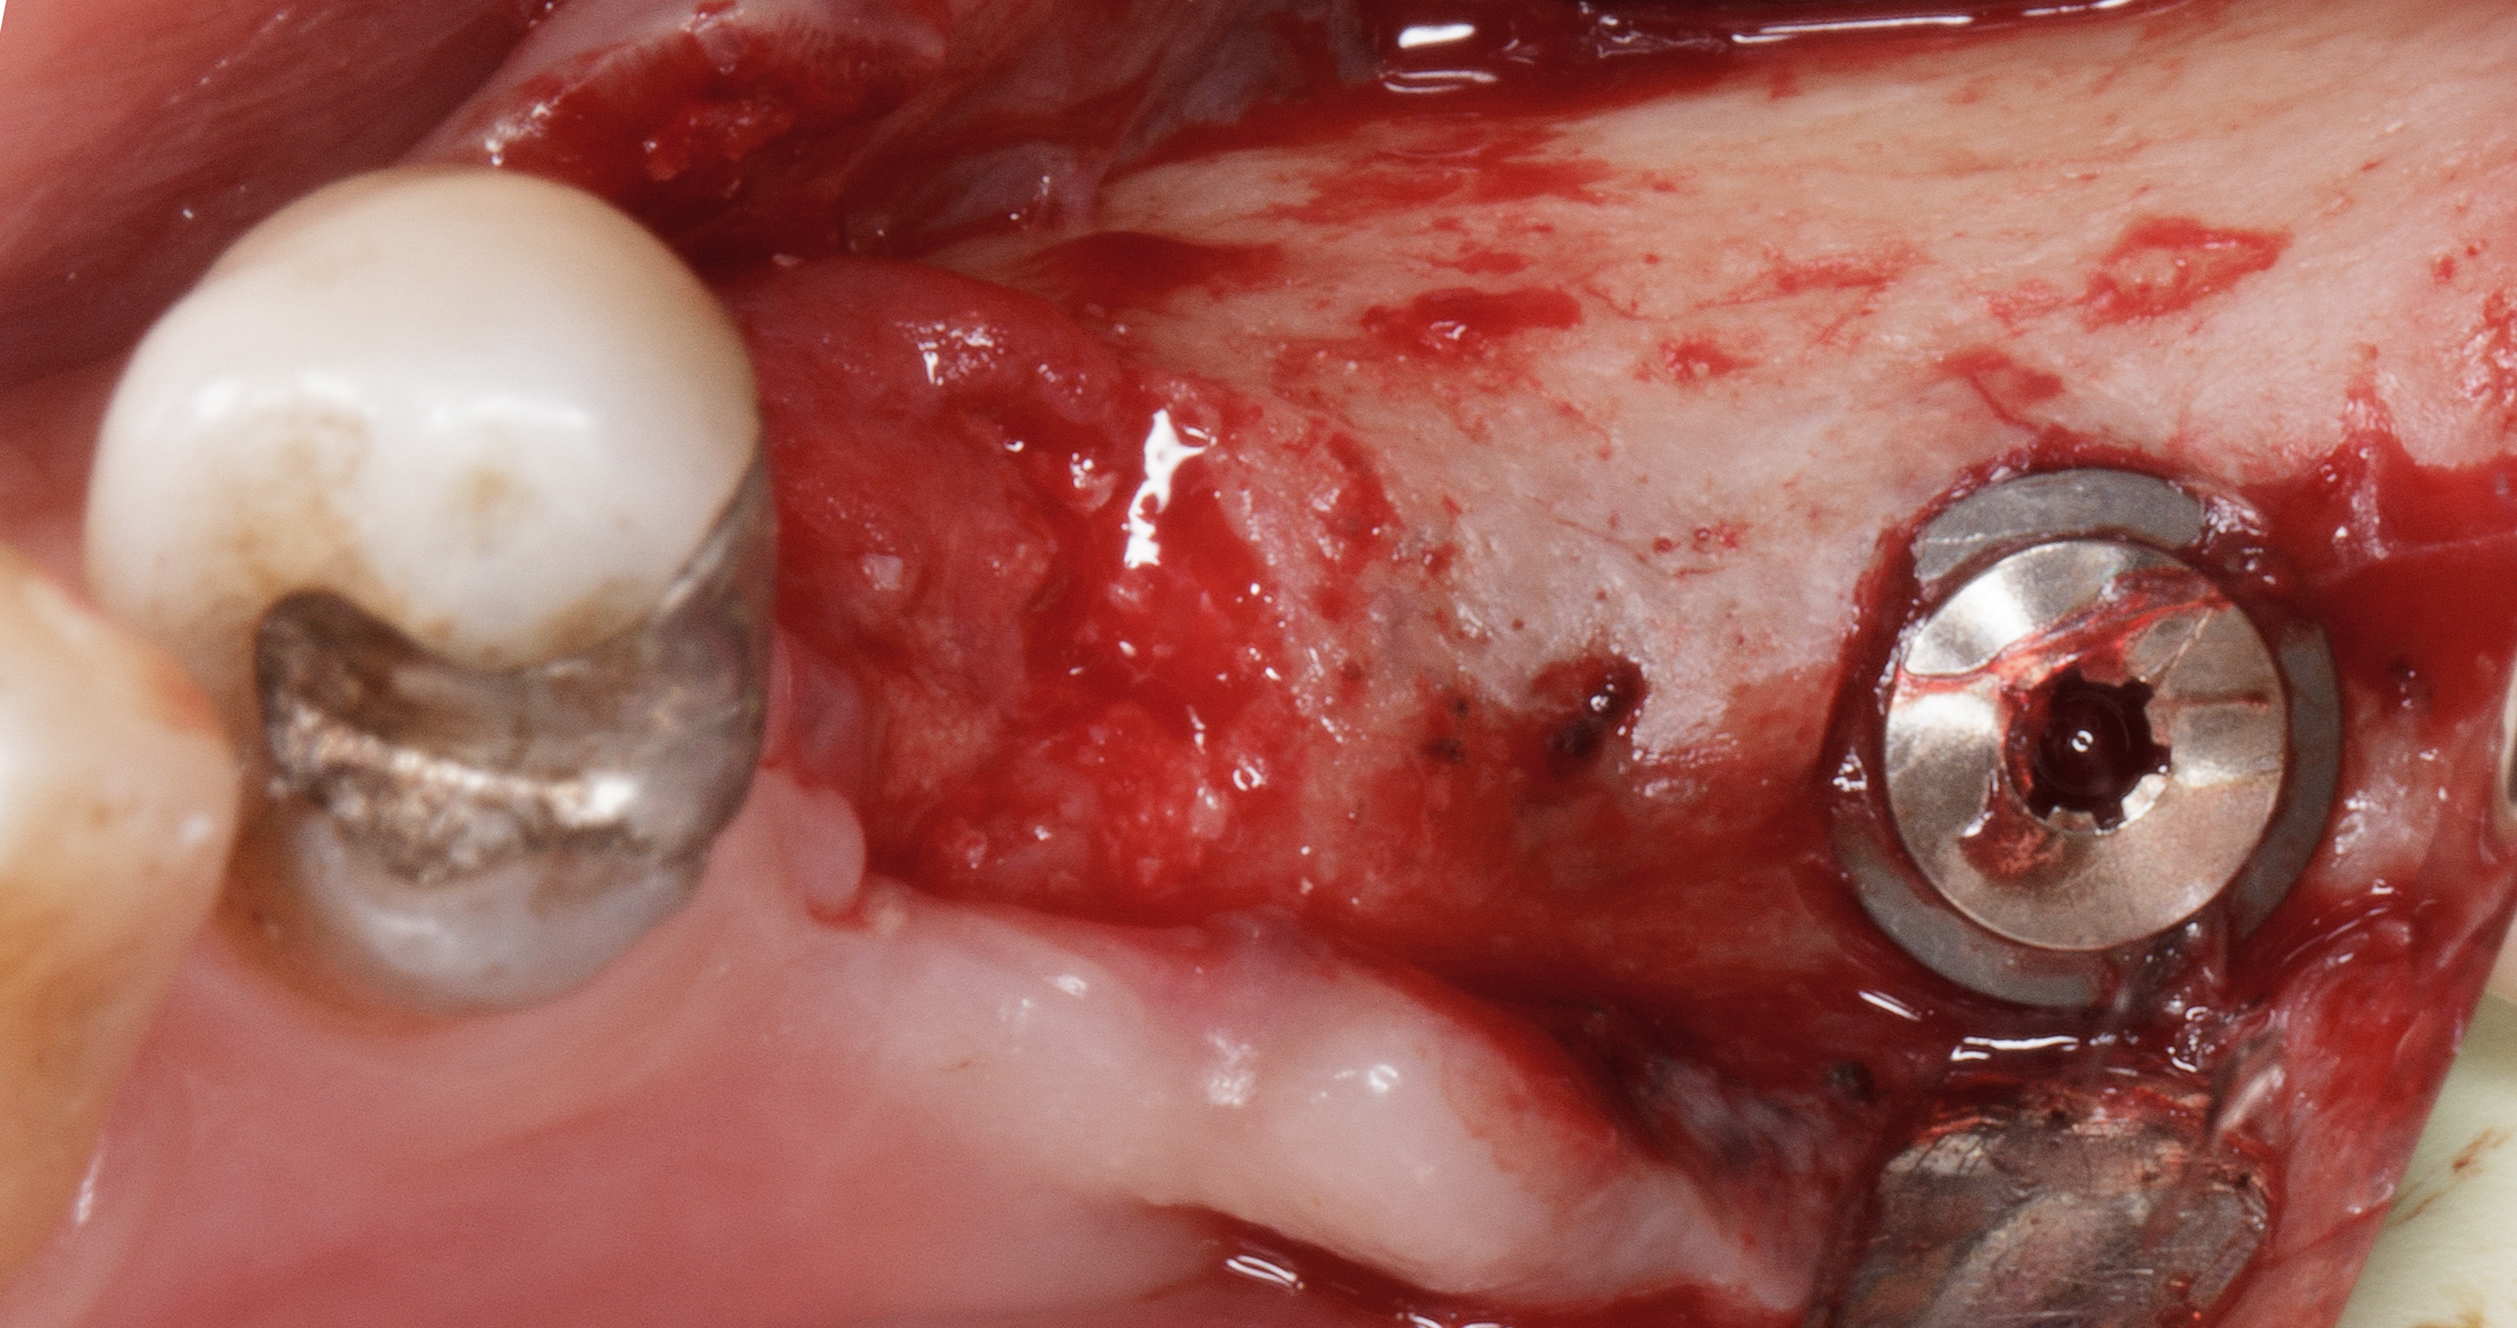

Dopo sei mesi dall’intervento di preservazione alveolare si inserisce un impianto differito in posizione 4.5.

Dopo esecuzione di lembo mucoperiosteo con una incisione di prolungamento mesiale a preservazione papillare, si osserva la presenza di tessuto osseo compatto in posizione premolare.

La corticale vestibolare e crestale non è ancora completamente formata, ma la visione in senso occlusale mostra come il tessuto osseo, che è ancora in fase di mineralizzazione, sia oltre il limite del bone housing dell’alveolo originario.

Si è ottenuta una preservazione del volume osseo oltre il 100% (Figure 18-19).

Il tunnel implantare è molto vascolarizzato. Viene inserito un impianto Neoss Tapered 4,5x11 mm, bone level, con torque di inserimento di 60 Ncm e ISQ 75 (Figure 20-22).